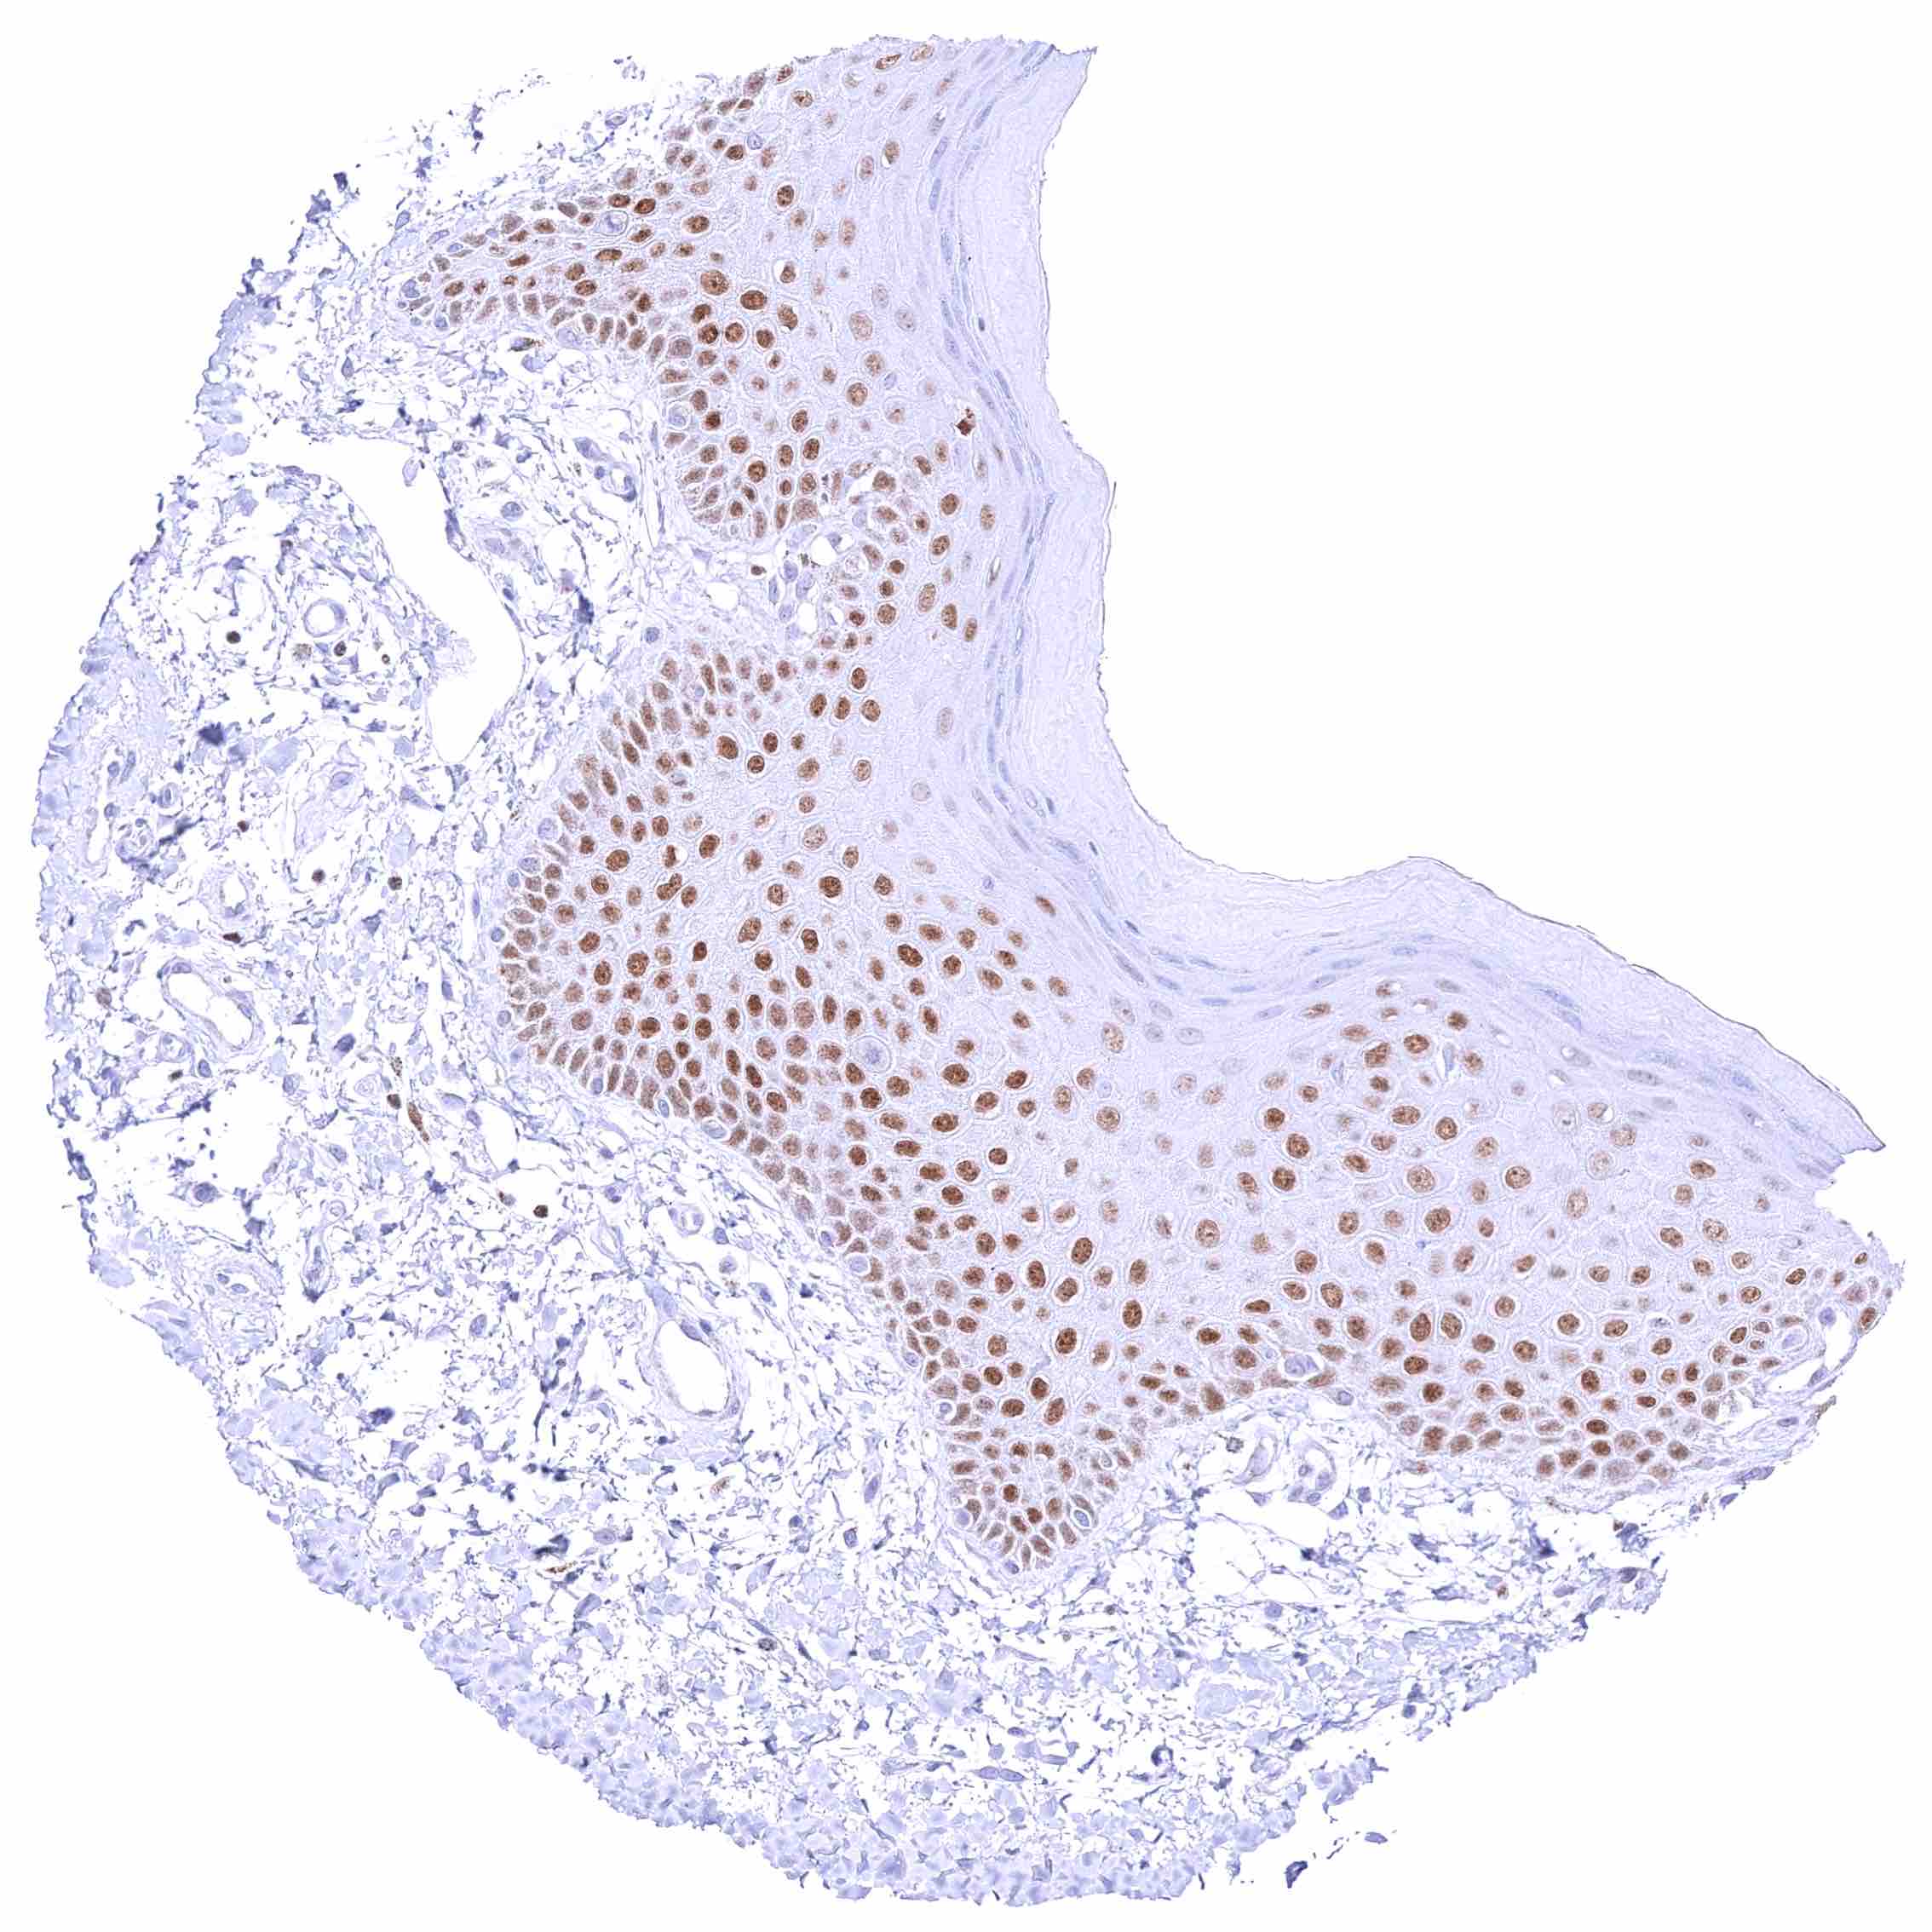

Skin – Strong nuclear GATA3 staining of squamous epithelial cells.

Skin, anal canal – Weak to moderate nuclear GATA3 staining of squamous epithelial cells. The staining predominates in the lower half of the epidermis.

Skin, hair follicel and sebaceous glands – Strong nuclear GATA3 staining of squamous epithelial cells, cells of hair follicles, and peripheral germinative cells of sebaceous glands. Nuclear GATA3 staining is faint or absent in cells of sebaceous glands.